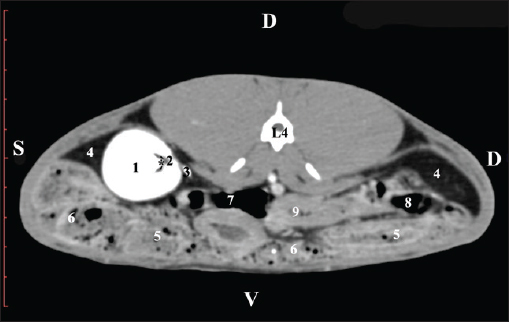

Fig. 9. Pre-contrast computed tomography (CT) anatomical scan of the regio-abdominis media at the caudal L3 edge level. (1) Ren dexter; (2) adipose collections; (3) cecum; (4) colon ascendens; (5) jejunum; (6) pars ascendens of the duodenum; (7) colon descendens. The pre-contrast anatomical scan at the L4 level provided data about the location of the renal pelvis within the renal sinus. The initial part of the pelvis renalis appeared as a distinct funnel-shaped hypoattenuated soft tissue, whose central part was widened and formed the recessus renalis. The transition of the narrowed end of the renal pelvis into the hypoattenuated left ureter was without a sharp boundary. The left kidney was in contact with the cecum, colon ascendens, and colon transversum ventrally. Crista renalis was observed as a hypoattenuated linear soft tissue finding (Figs. 10 and 11).

Fig. 10. Pre-contrast computed tomography (CT) anatomical scan of the regio-abdominis media at the cranial L4 edge level. (1) Ren sinister; (2) pelvis renalis and crista renalis; (3) ureter; (4) cecum; (5) colon ascendens; (6) colon transversum; (7) colon descendens; (8) adipose collections.

Fig. 11. Pre-contrast computed tomography (CT) anatomical scan of the regio-abdominis media at the caudal L4 edge level. (1) Ren sinister; (2) pelvis renalis; (3) ureter; (4) adipose collections; (5) cecum; (6) colon ascendens; (7) colon transversum; (8) colon descendens; (9) mesenterium; (white arrows) recessus renalis; (*) crista renalis. The L5 scan revealed the caudal end of the left kidney. It was adjacent to some small intestinal segments, including the duodenal pars ascendens, ileum, cecum, and colon ascendens (Figs. 12 and 13).